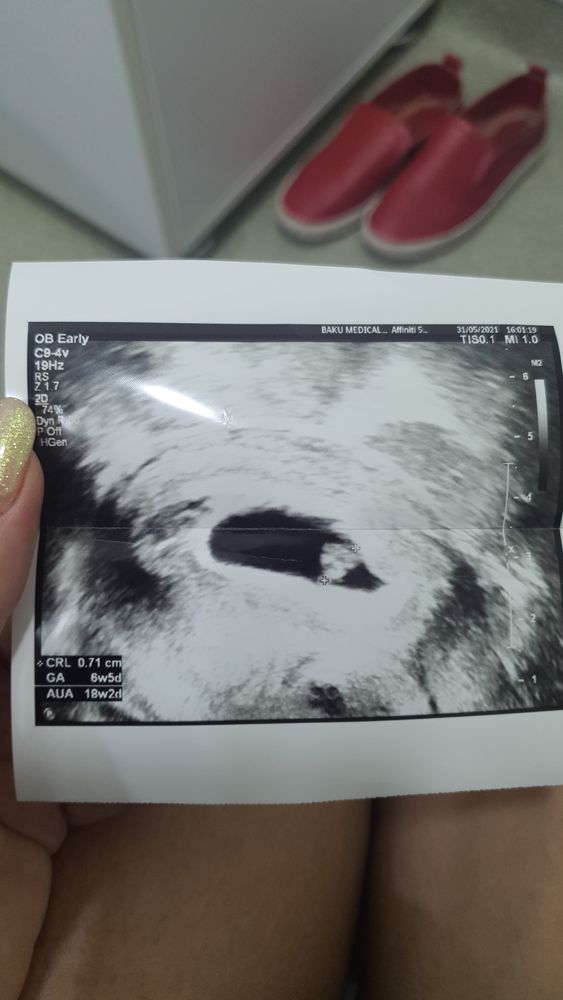

Макуся, Изображение

Изображение Lerchik , не много?

Макуся, Неа , посмотрели узи сегодня говорят , что даже видно , что эмбриону все хватает хороший мешочек, у меня в поддержке укол, гель , дюфастон, прогинова, так что на разницу со мной не обращайте внимание , у меня все искусственно , поэтому такая поддержка

Изображение Lerchik , вот размеры и сроки

Макуся, странно как то все у Вас , у меня 7 недель и 5 дней и 2,2 мм , а у Вас 1,75мм и не смутило 🤷‍♀️

Макуся, или это 17 мм ?

Lerchik , да. 17 мм

Изображение

Макуся, не у меня не такой ))) у желтый мешочек и маленькая палочка )

Lerchik , посмотрите там в левом нижнем углу есть CRL- это КТР- это было неделю назад. Тогда сердцебиение было